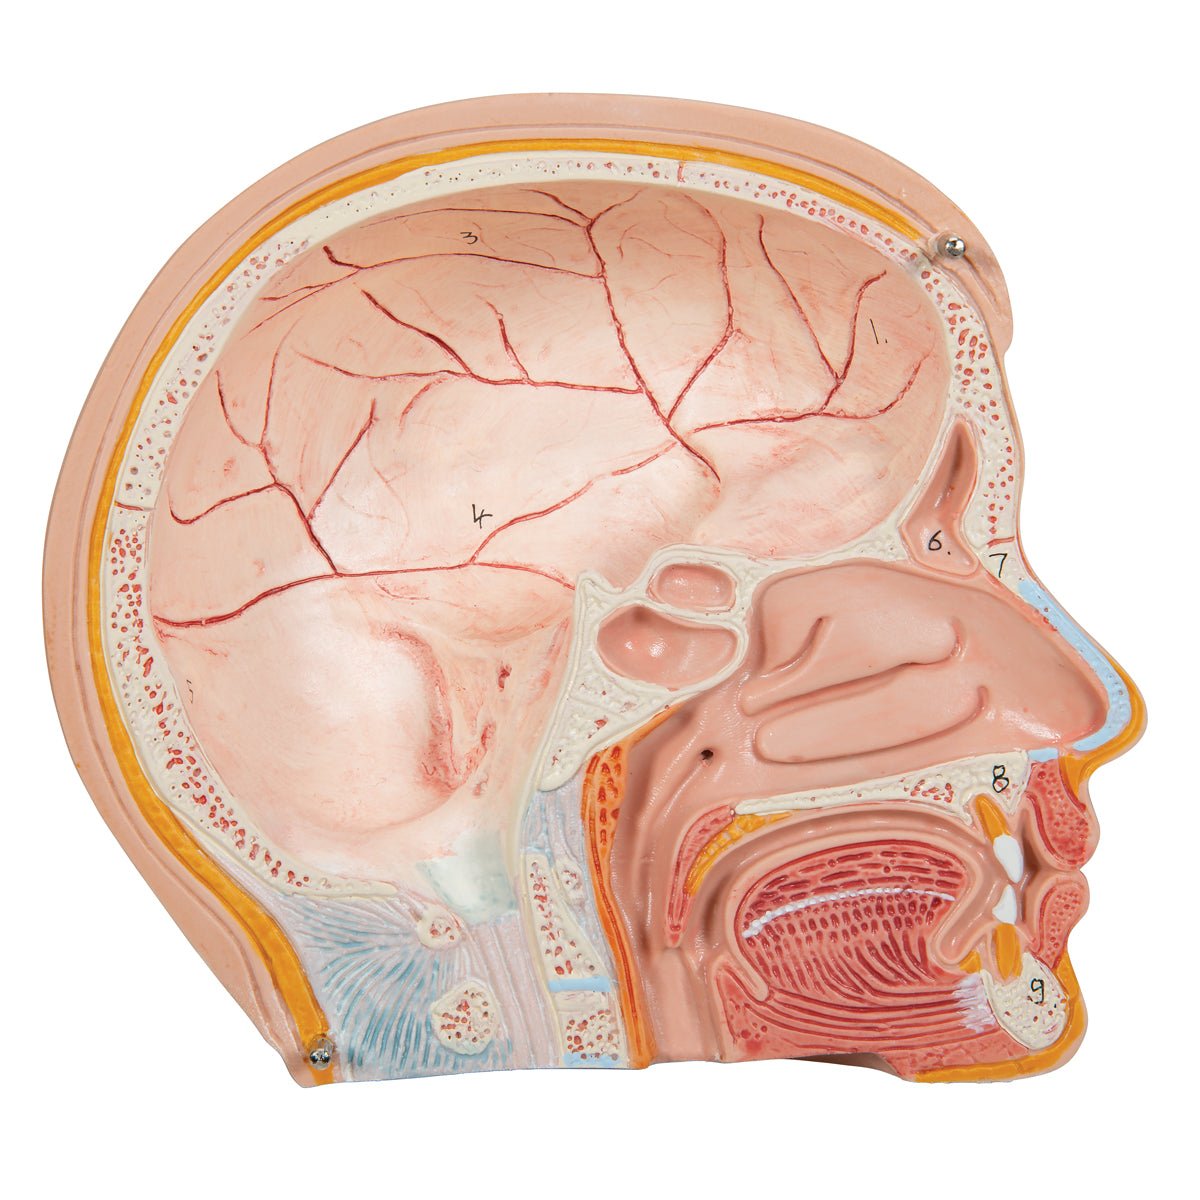

Salg af anatomiske modeller er det bærende element i eAnatomi, selvom vi også bruger mange ressourcer på at udvikle vores egne anatomiske materialer som fx plakater. Anatomiske modeller anvendes til forskellige formål og kan både vise afgrænset væv, organer samt organsystemer. Søger du en simpel model af knoglevæv eller måske en avanceret torso-model baseret på MRI teknologi, kan du finde det hele på eanatomi.com.